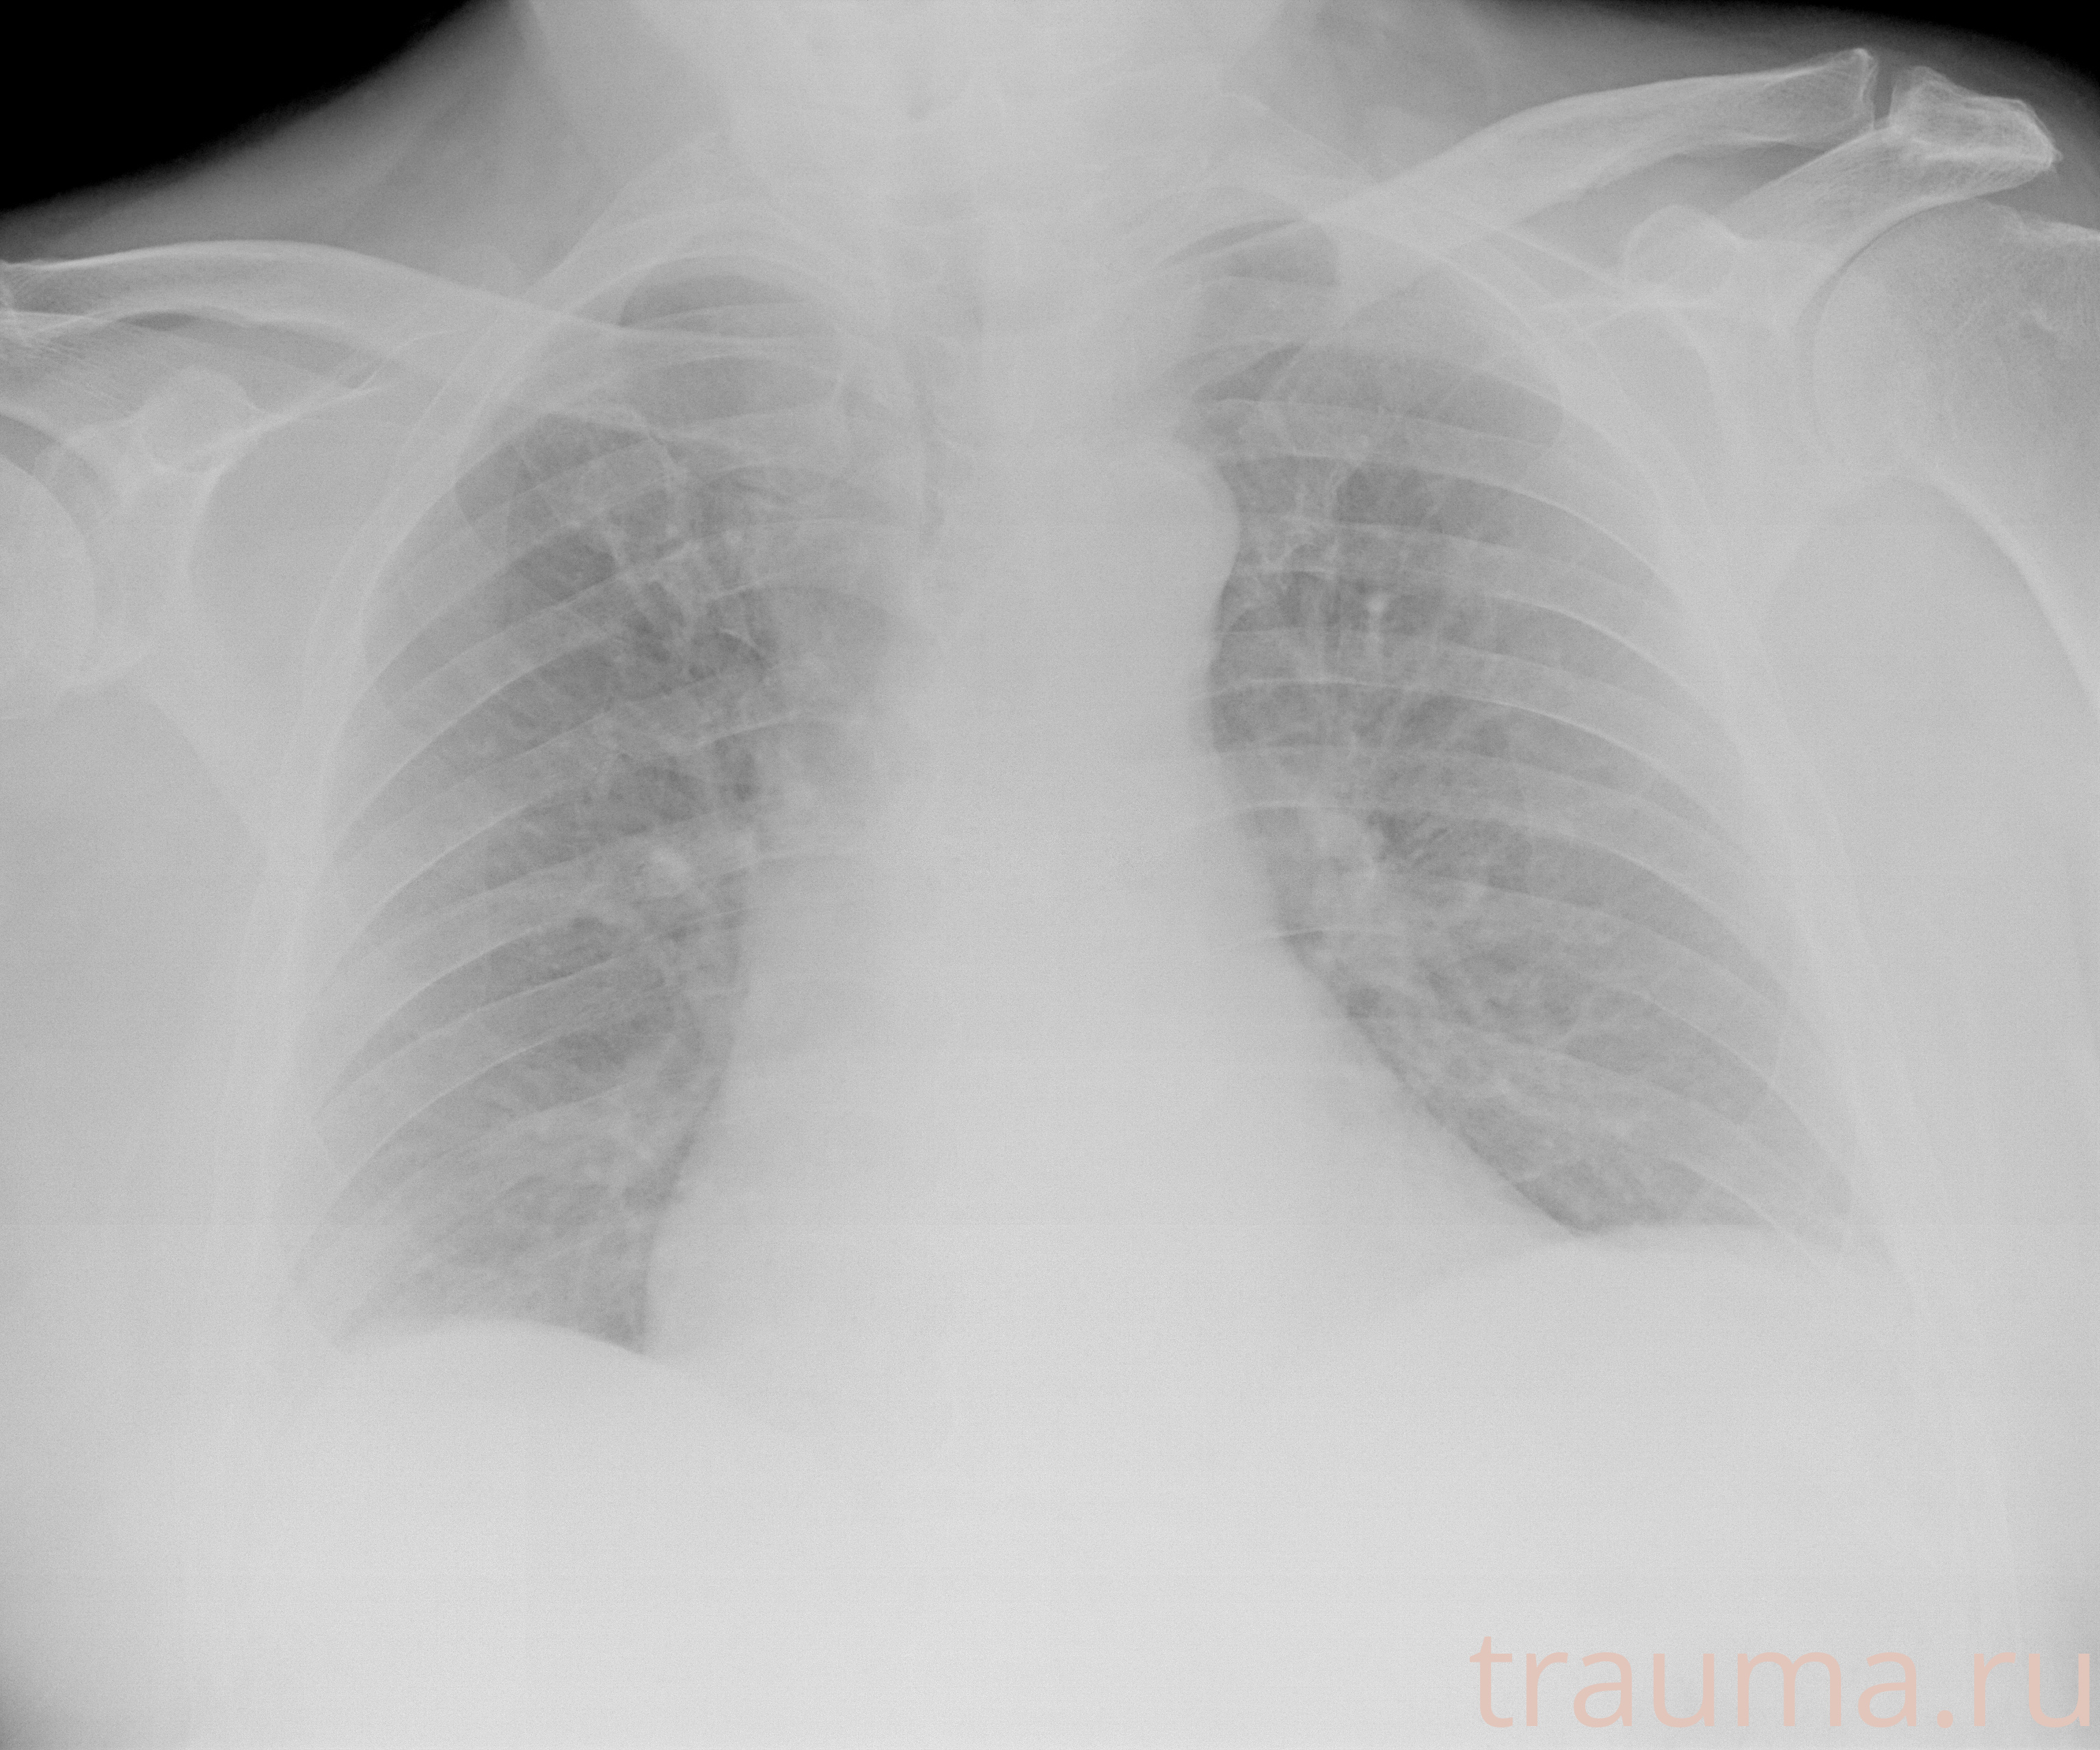

Рентген на дому: по вашему адресу приезжает врач-рентгенолог, травматолог-ортопед с мобильным рентгеновским аппаратом, проводит диагностику травмы или заболевания, делает необходимые рентгенограммы, дает рекомендации по дальнейшему лечению. Получить качественные снимки в домашних условиях возможно благодаря уникальной методике, разработанной МосРентген Центром для института  Склифосовского